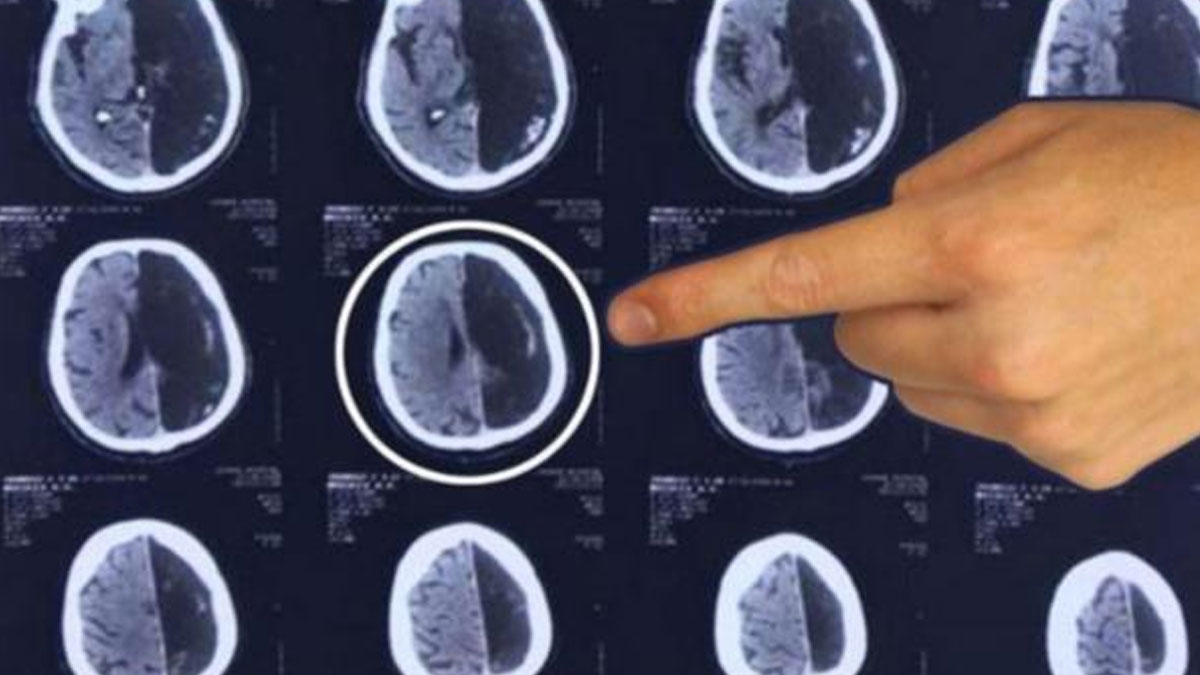

Rusya'da 60 yaşındaki adamın gittiği hastanede beyninin yarısı olmadığı ortaya çıktı. Emekli mühendis, "Kusursuz bir hayat yaşadım, meşhur olmak istemiyorum" dedi ve hastaneden ayrıldı.

Moskova'da bir sağlık merkezinde görev yapan doktorlar, bir hastanın beyninin yarısının olmadığını tespit etti. Hastanın vücut fonksiyonlarında hiçbir eksiklik görülmemesi büyük şaşkınlık yarattı.

Rus basınında yer alan habere göre Moskova Bölgesi'ndeki bir sağlık merkezine 'geçici iskemik atak' şikayetiyle başvuran hastanın beyninin yarısı olmadan yaşadığı ortaya çıktı.

Doktorlar, sıradışı klinik vaka karşısında şaşkınlıklarını gizlemezken 60 yaşındaki emekli mühendisin tüm vücut fonksiyonlarını eksiksiz kullanabilmesi bu bulguyu daha şaşırtıcı kıldı.